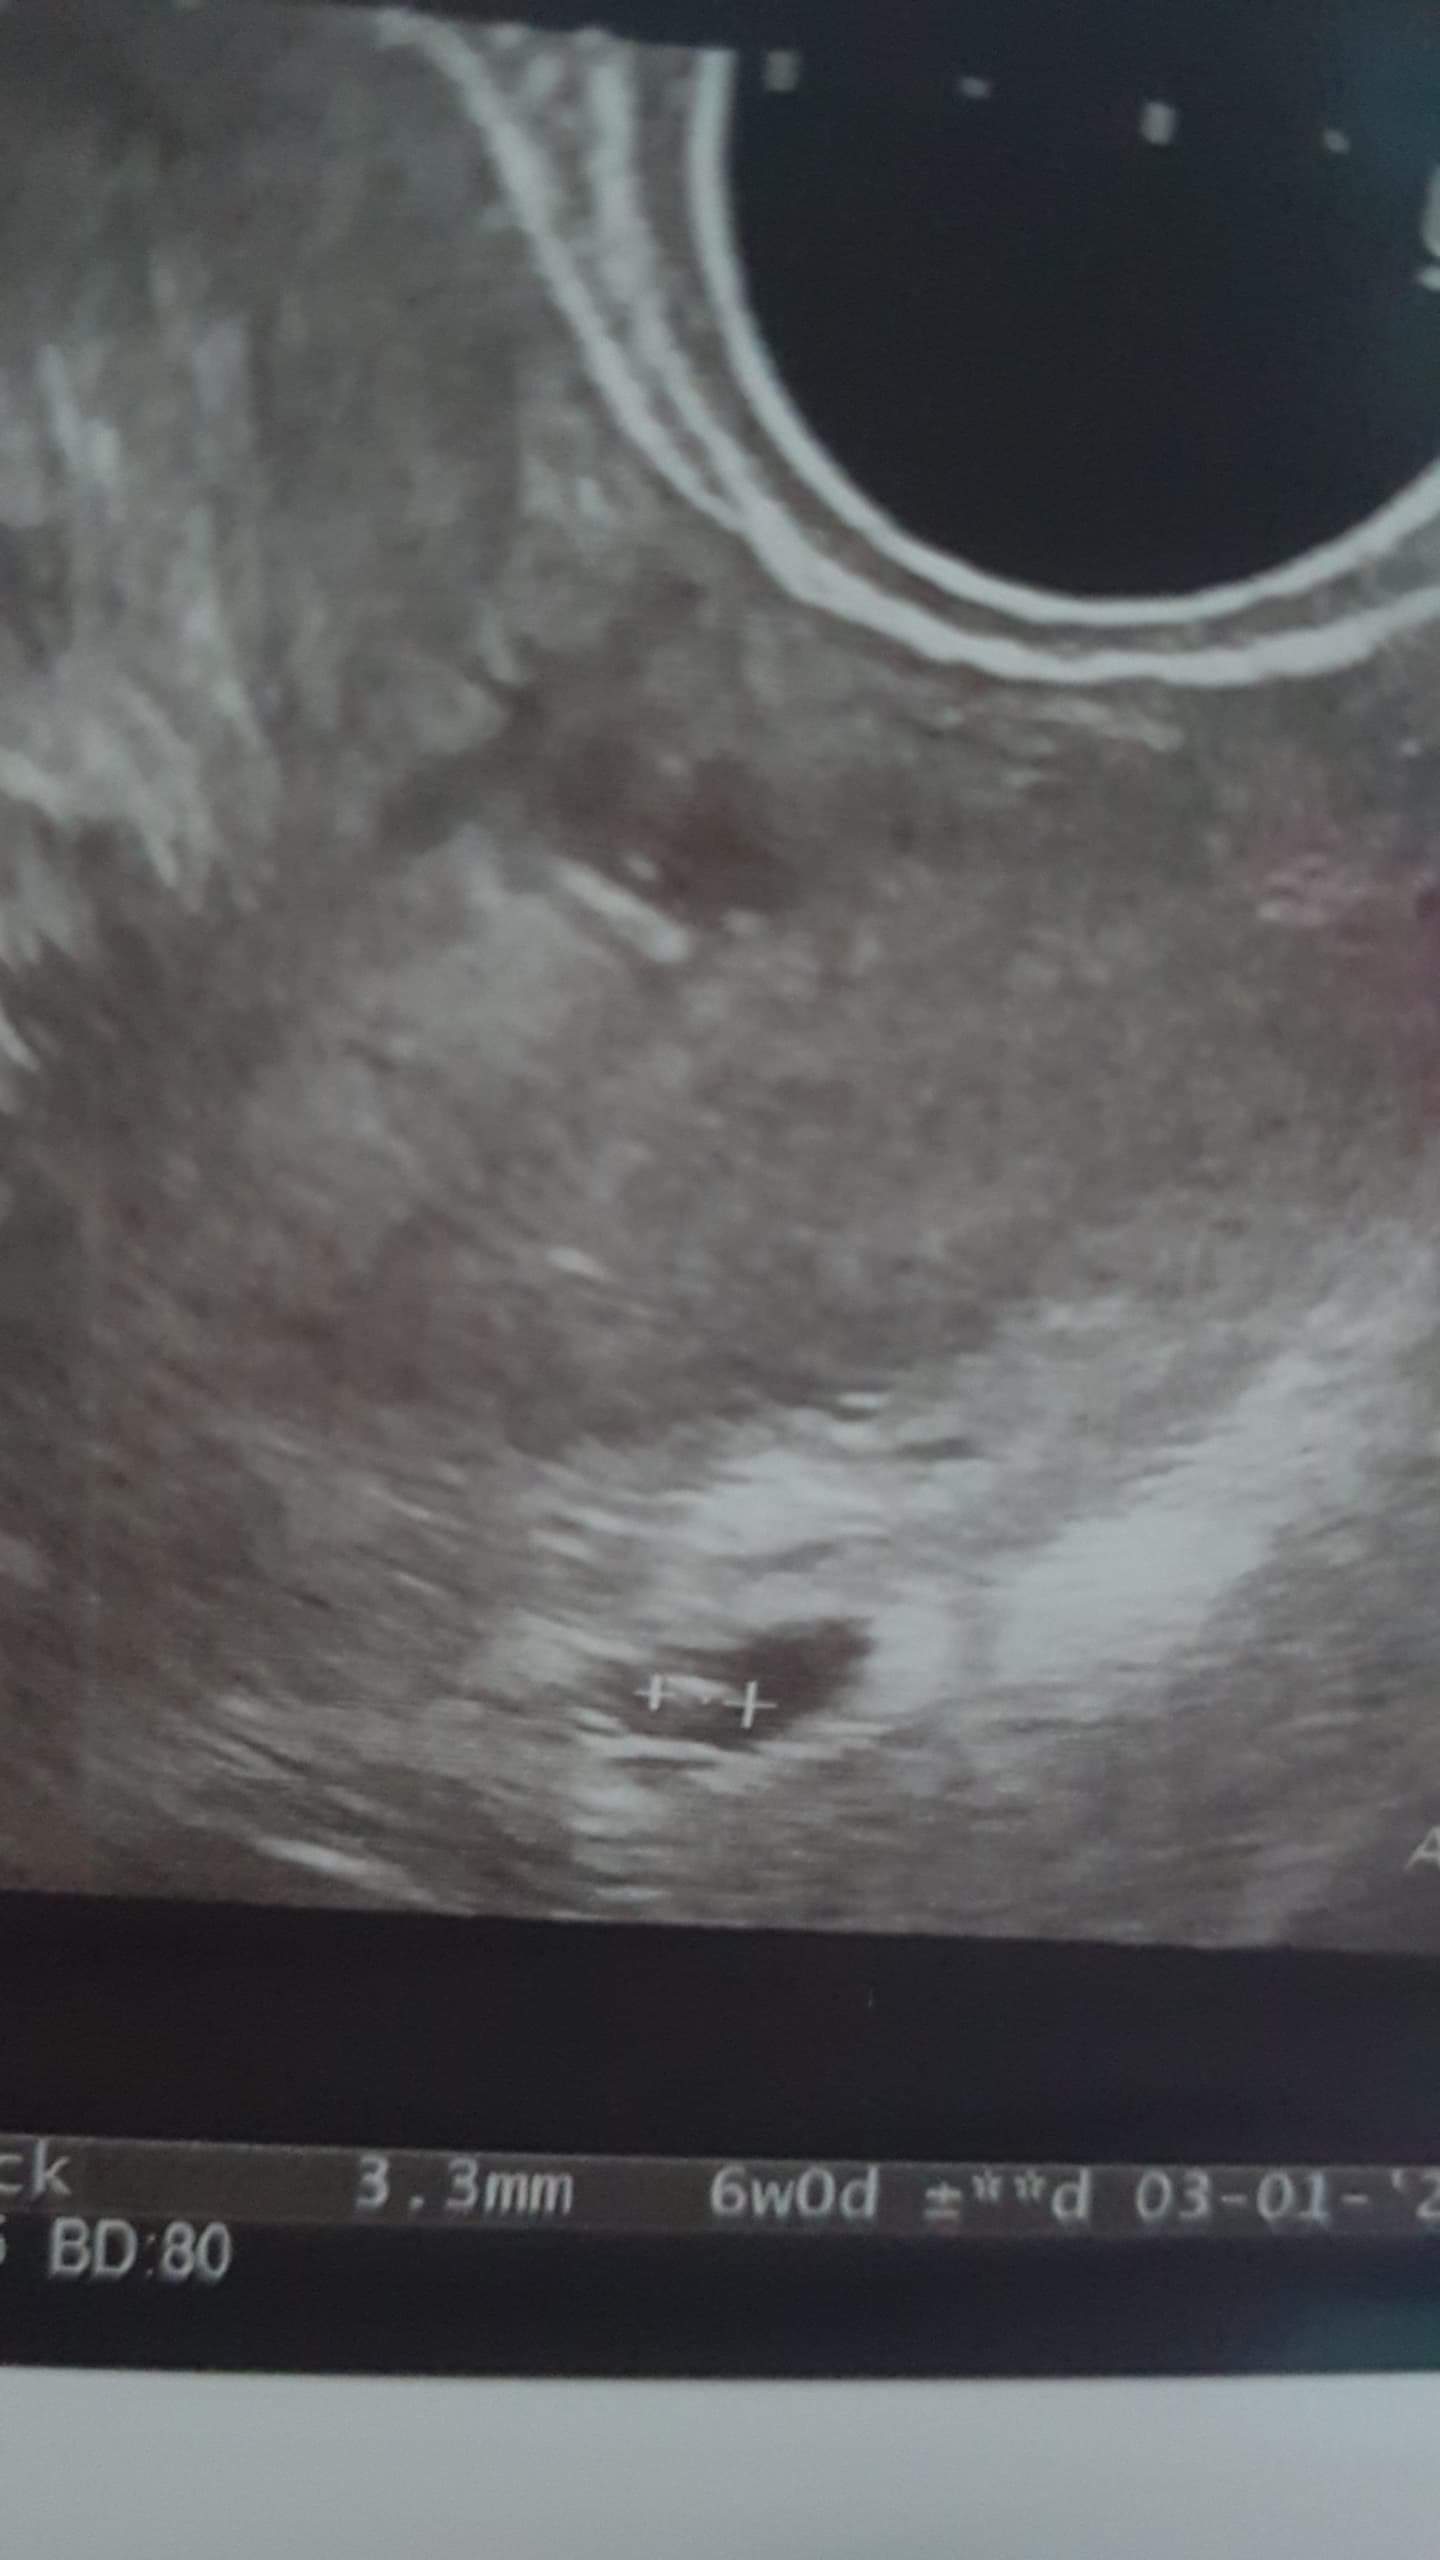

Ja coś pokręciłam... Ciężko mi rozszyfrować na usg co jest co 😂 teraz zaskoczyłam, że maleństwo ma 3,3mm a cały pęcherzyk dookoła 44 😁

Załączniki

• received_473411880539182.jpeg

received_473411880539182.jpeg

108,4 KB · Wyświetleń: 127